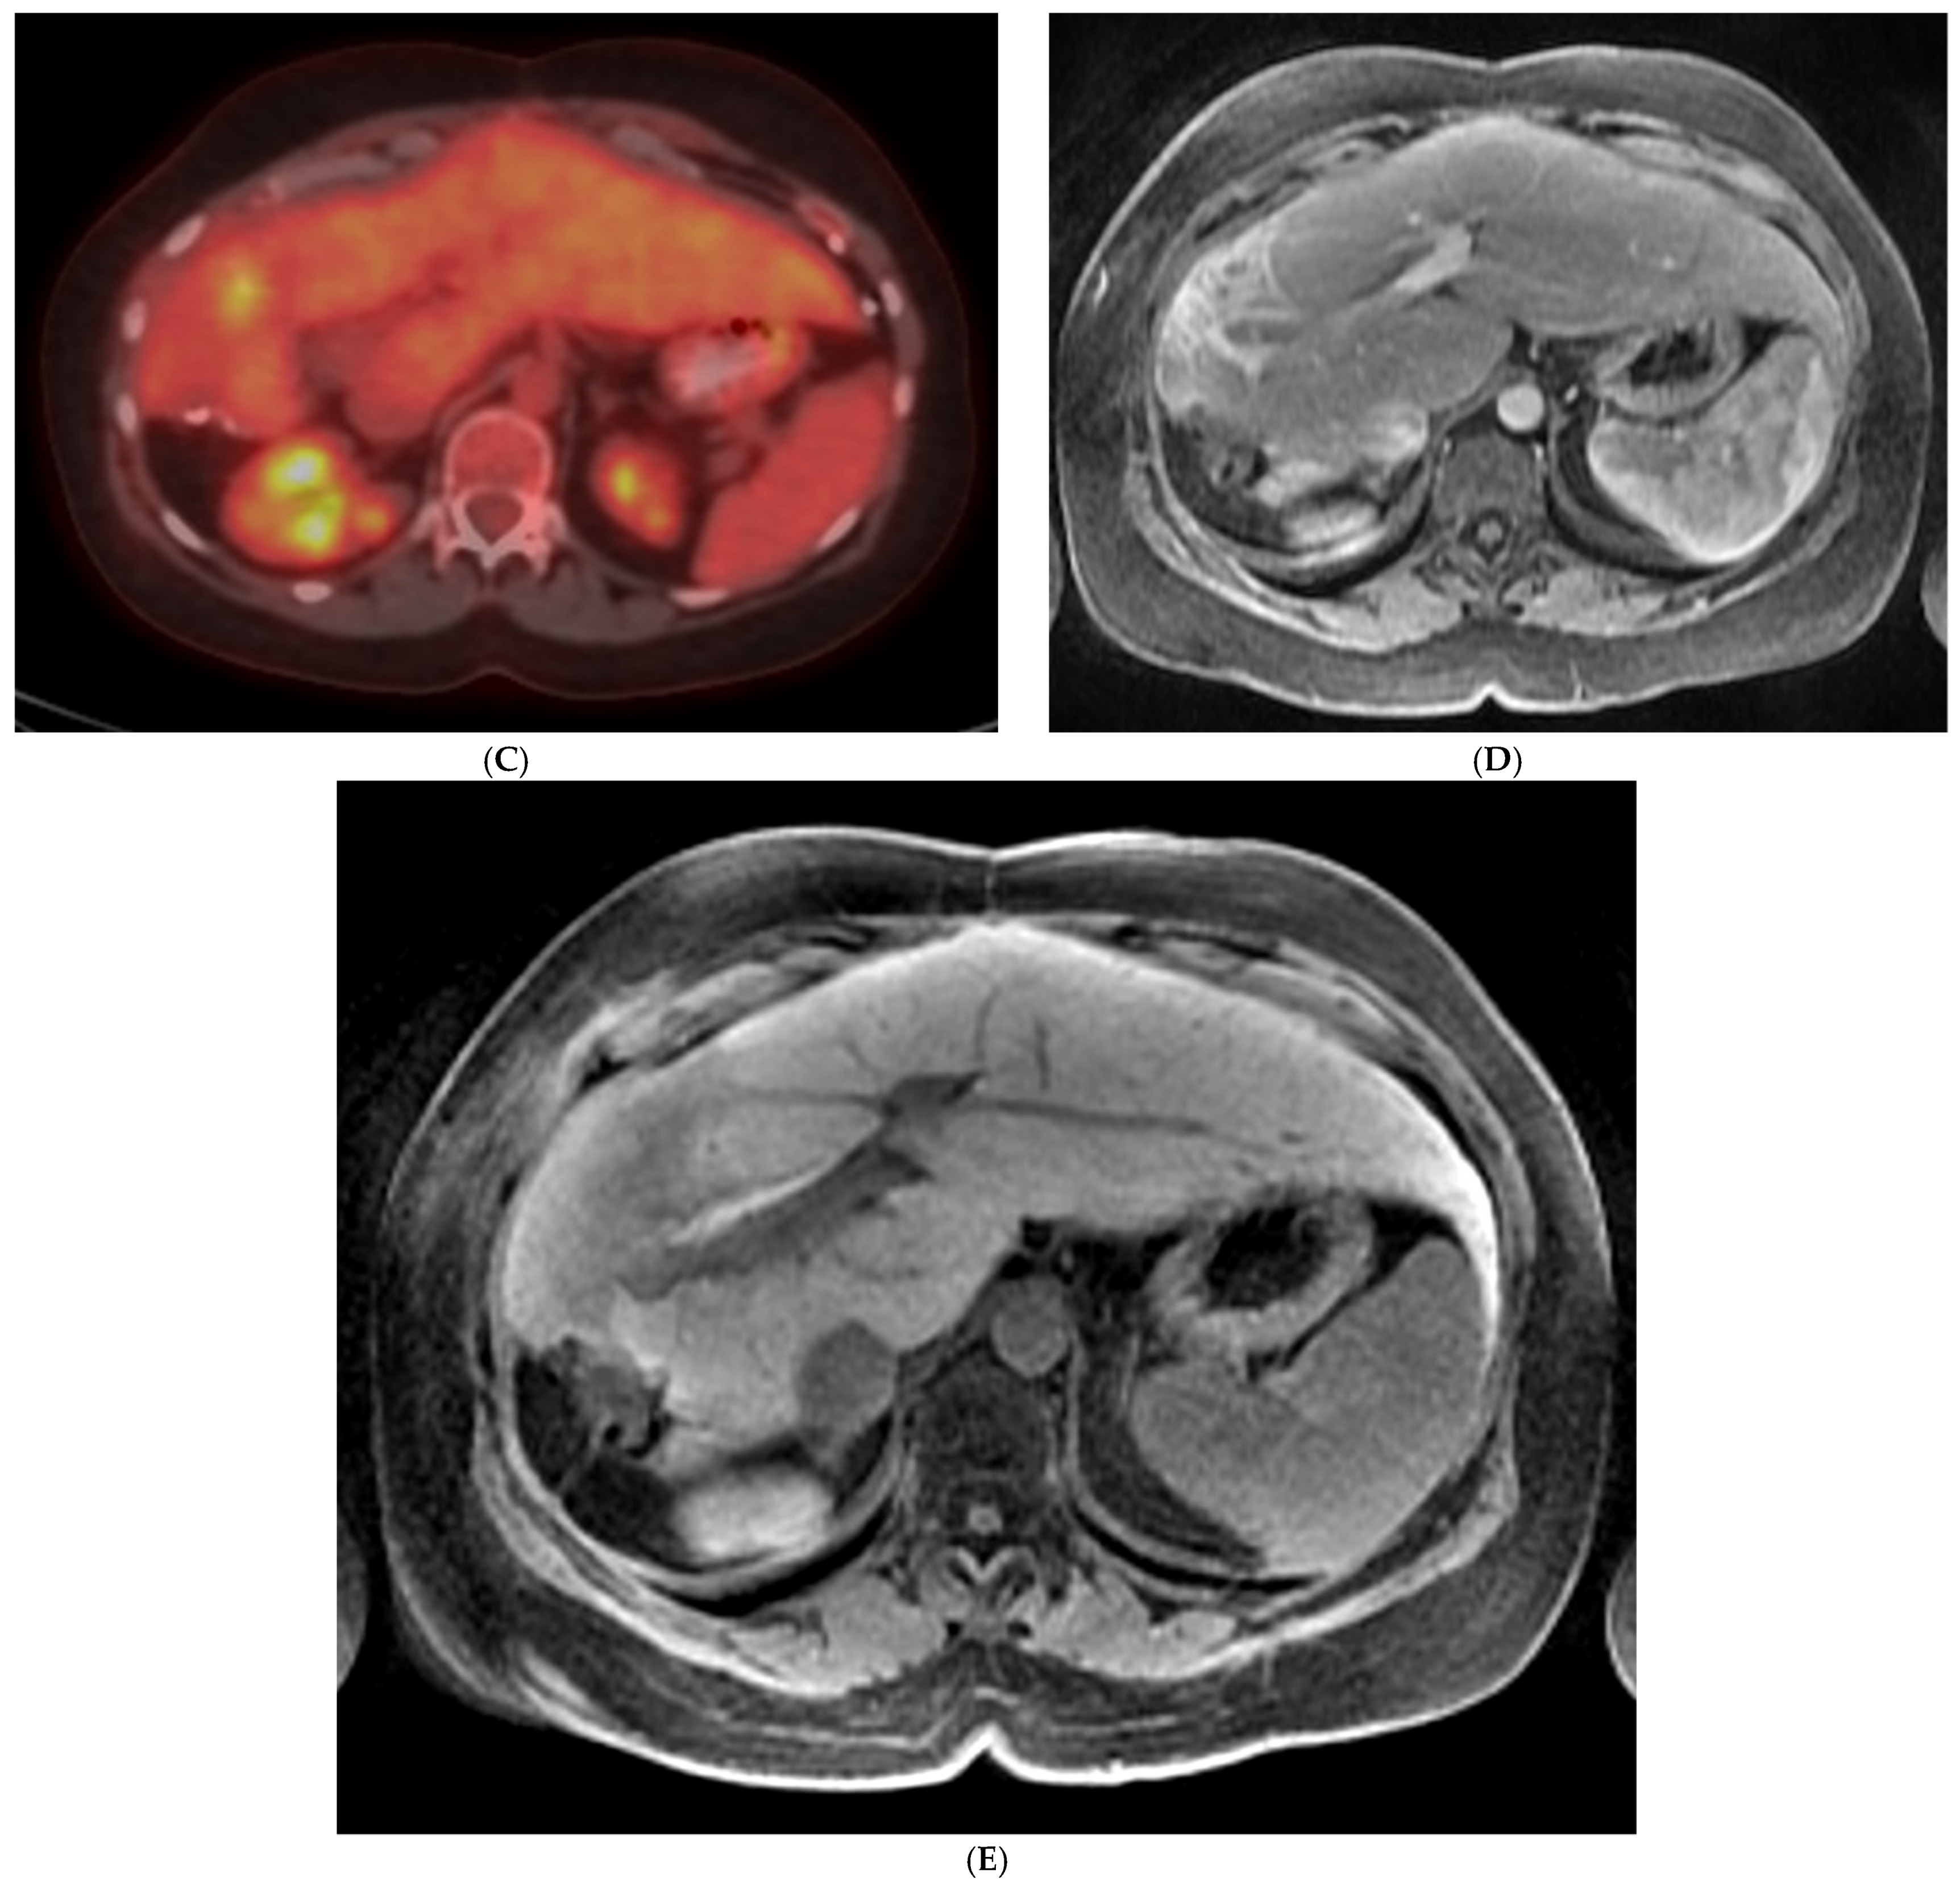

- Atassi, B.; Bangash, A.K.; Bahrani, A.; Pizzi, G.; Lewandowski, R.J.; Ryu, R.K.; Sato, K.T.; Gates, V.L.; Mulcahy, M.F.; Kulik, L.; et al. Multimodality Imaging Following 90Y Radioembolization: A Comprehensive Review and Pictorial Essay. RadioGraphics 2008, 28, 81–99. [Google Scholar] [CrossRef]

- Shady, W.; Kishore, S.; Gavane, S.; Do, R.K.; Osborne, J.R.; Ulaner, G.A.; Gonen, M.; Ziv, E.; Boas, F.E.; Sofocleous, C.T. Metabolic Tumor Volume and Total Lesion Glycolysis on FDG-PET/CT Can Predict Overall Survival after 90Y Radioembolization of Colorectal Liver Metastases: A Comparison with SUVmax, SUVpeak, and RECIST 1.0. Eur. J. Radiol. 2016, 85, 1224–1231. [Google Scholar] [CrossRef] [PubMed]

- Sabet, A.; Meyer, C.; Aouf, A.; Sabet, A.; Ghamari, S.; Pieper, C.C.; Mayer, K.; Biersack, H.-J.; Ezziddin, S. Early Post-Treatment FDG PET Predicts Survival after 90Y Microsphere Radioembolization in Liver-Dominant Metastatic Colorectal Cancer. Eur. J. Nucl. Med. Mol. Imaging 2015, 42, 370–376. [Google Scholar] [CrossRef] [PubMed]

- Shady, W.; Sotirchos, V.S.; Do, R.K.; Pandit-Taskar, N.; Carrasquillo, J.A.; Gonen, M.; Sofocleous, C.T. Surrogate Imaging Biomarkers of Response of Colorectal Liver Metastases after Salvage Radioembolization Using 90Y-Loaded Resin Microspheres. Am. J. Roentgenol. 2016, 207, 661–670. [Google Scholar] [CrossRef]

- Wong, C.; Salem, R.; Raman, S.; Gates, V.L.; Dworkin, H.J. Evaluating 90Y-Glass Microsphere Treatment Response of Unresectable Colorectal Liver Metastases by [18F]FDG PET: A Comparison with CT or MRI. Eur. J. Nucl. Med. Mol. Imaging 2002, 29, 815–820. [Google Scholar] [CrossRef]